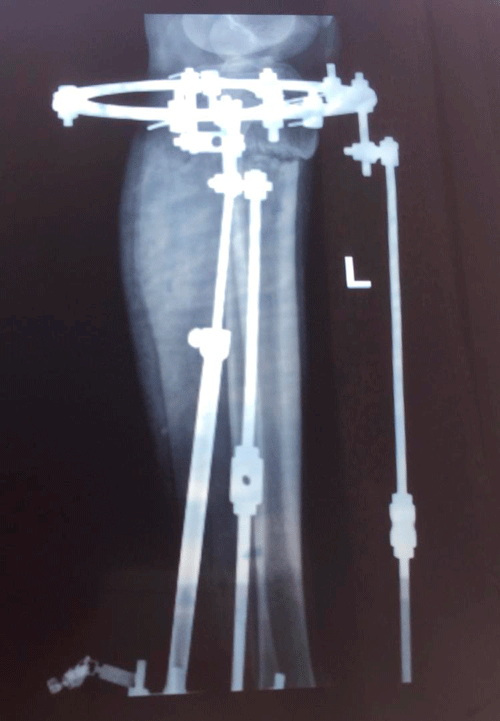

Рентген на фиксации(после исправления деформации ног)

IMG_1194-17-02-19-09-10.JPG